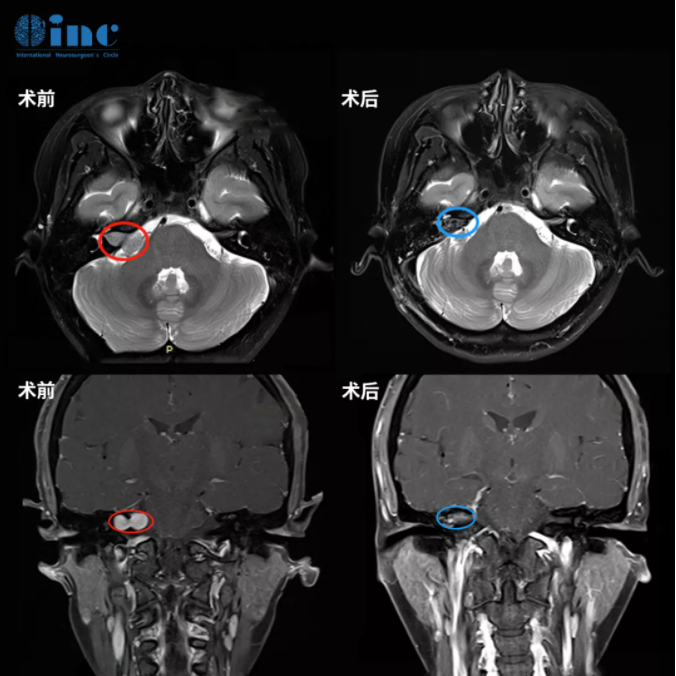

“手术要么不做,做就要做好,第一次手术尽量全切,而且一定不能面瘫”——曾出现4次右耳听力下降、饱受听神经瘤折磨的姜女士无论如何也无法接受自己再因为手术而面瘫,进而也坚定了这样的治疗思路。为此,她找了很多国外专家咨询,最后终于在INC德国巴特朗菲教授得到了满意的手术评估结果——可以全切肿瘤,暂时性面瘫的风险是7%,永久性面瘫的风险是1%,复发概率可能只有2-3%。

于是姜女士赴德手术,巴教授就像邮件中说的那样,为她全切了肿瘤,还保住了面神经。她醒来的第一句话就是:“太好了,我真的没有面瘫!”,术后第2天她就转出了ICU回到普通病房,教授每天都会查房,还会耐心地解答问题,在医护人员的精心照料下,术后1周她就出院了。她还特意和我们提到,她的手术创口很小,就在耳后,所以不需要剃头!别人几乎看不出来自己做了开颅手术,就像没得过脑瘤一样。